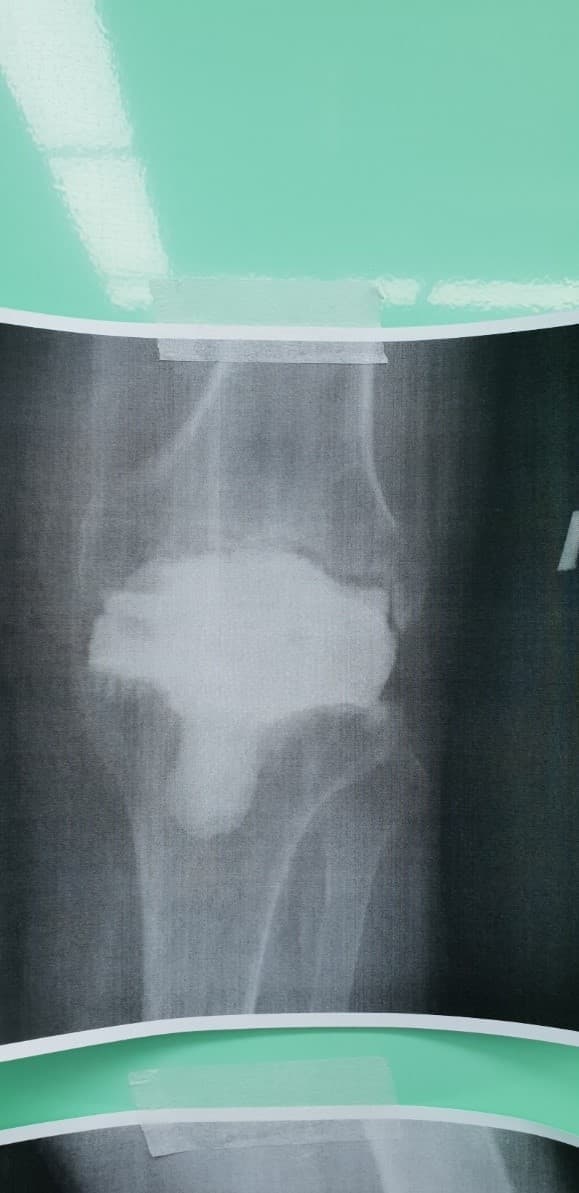

Үе дайрсан ясны анхдагч хавдар, ясны дутмагшлын үед хийгдэх мэс засалimage8Үе дайрсан ясны анхдагч хавдар, ясны дутмагшлын үед хийгдэх мэс засалimage9

Зураг 1. Гадна харагдах байдал: Зүүн дунд чөмөгний өвдөгний үе орчмын ясны хавдар, хавдар задар үхэжсэн байна.

Үе дайрсан ясны анхдагч хавдар, ясны дутмагшлын үед хийгдэх мэс засалimage10

А. Мэс засал хийсэн өвдөгний үе

Үе дайрсан ясны анхдагч хавдар, ясны дутмагшлын үед хийгдэх мэс засалimage11

Б. Бүтэн биеийн рентген зураг

Зураг 2. Мэс заслын дараах рентген зураг

Хавдрын улмаасмэс хийлгэсэнөвчтөнгүүд мэс заслын дараа 2-3 хоногийн дотор шууд гишгэж явж, мөчдийн үйл ажиллагаа хурдан сэргэж эхний 1 сард үений хөдөлгөөний далайц хэвийн болсон .